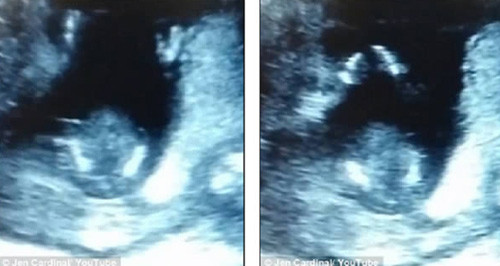

Jen Cardinal, bà mẹ sinh sống tại Olympia, Washington, Mỹ gần đây đã đăng tải một video siêu âm thai khiến người xem ngạc nhiên. Theo đó, trong video có thể thấy em bé 14 tuần tuổi đang vỗ tay như theo điệu nhạc.